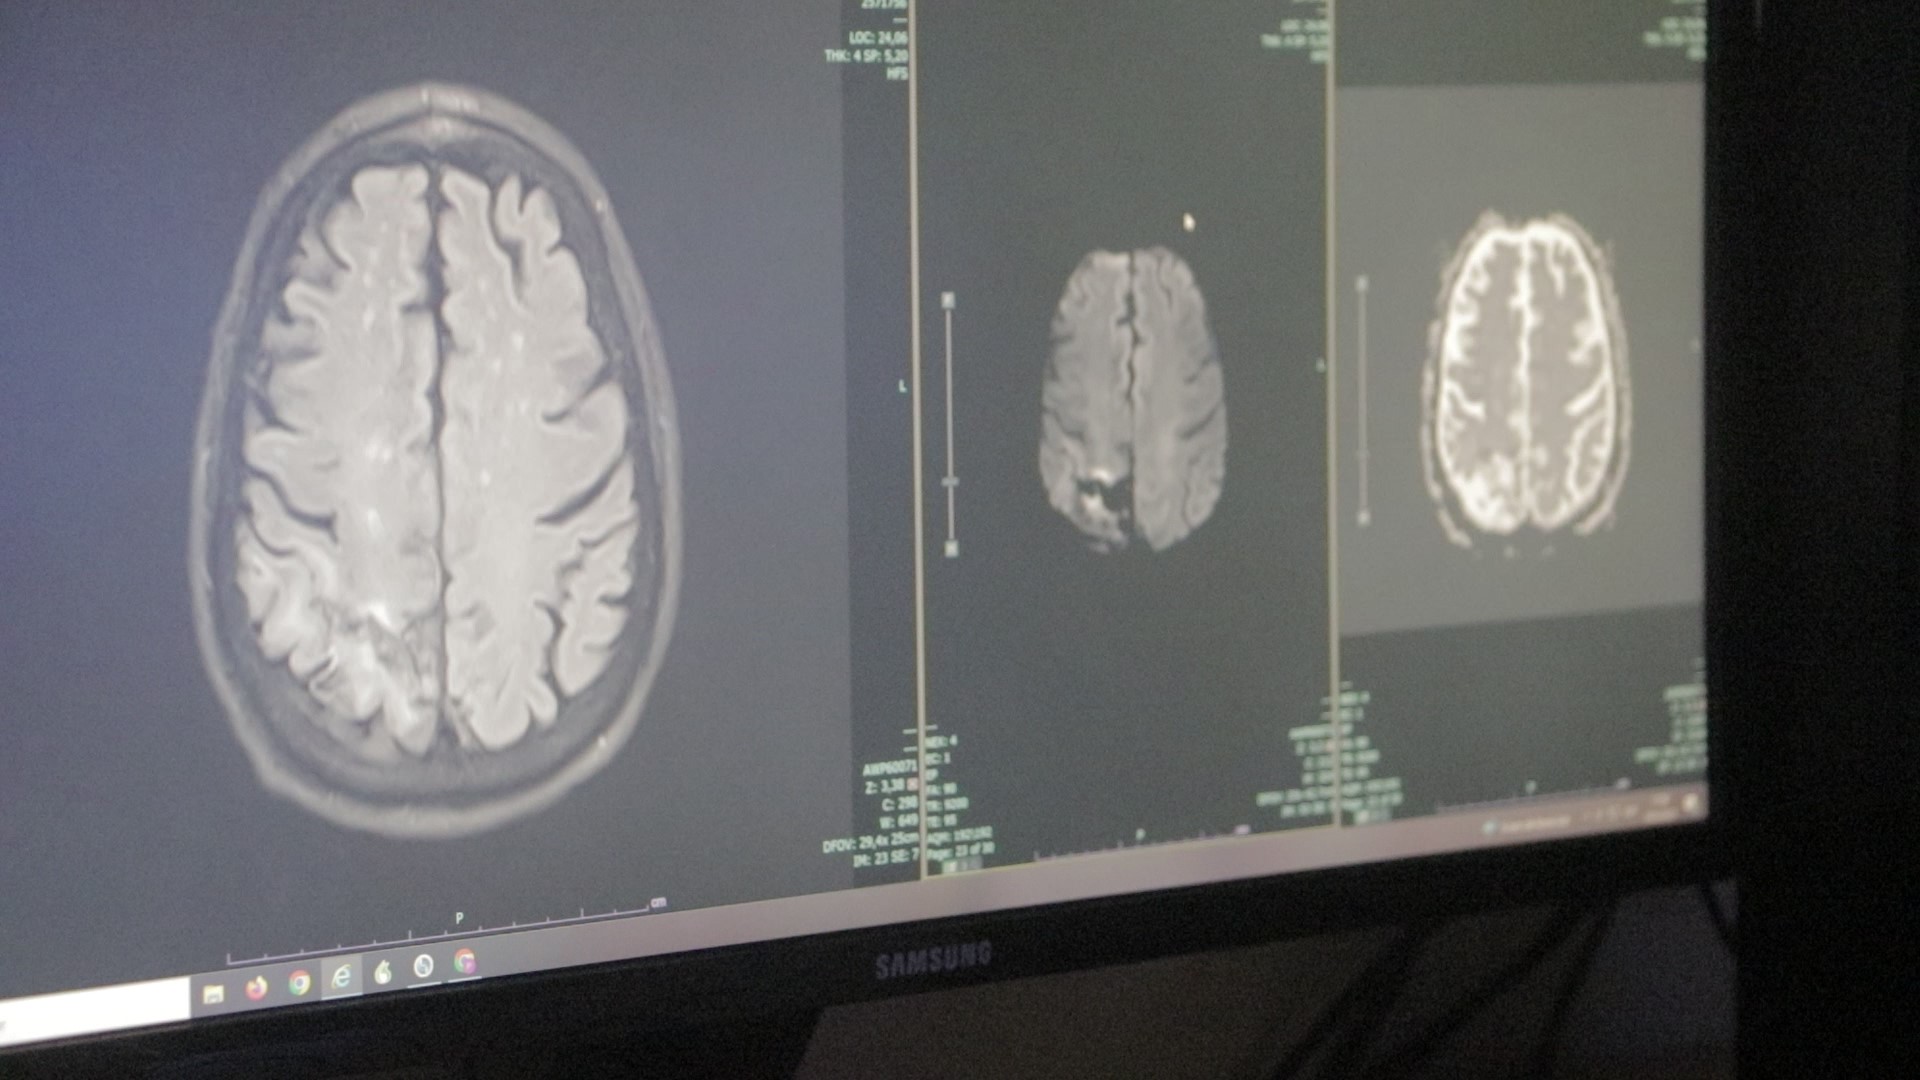

El Hospital Escuela de Agudos “Dr Ramón Madariaga” tiene un equipo de médicos neurólogos en un Servicio que atiende los diferentes tipos de accidentes cerebrovasculares (ACV). Existen dos más frecuentes que son el isquémico y el hemorrágico. Hay señales de alerta que permiten detectarlo a tiempo y reconocer los síntomas puede salvar vidas.

El Dr. Christian Bortoluzzi, del Servicio de Neurología del Madariaga explicó que el ACV o accidente cerebrovascular es una emergencia médica que se produce por la interrupción del flujo sanguíneo cerebral.

“Existen dos grandes tipos, uno es el isquémico que se produce por la oclusión de una arteria y el otro es el hemorrágico que se produce por la ruptura de una arteria. En ambos se produce la muerte neuronal”, sostuvo el profesional.